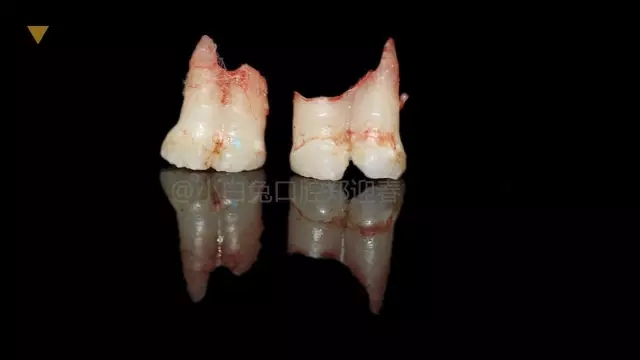

拔出后的離體牙

患兒,10歲,因上前牙未替換來診,查體:輕度反合,51和52、61和62均融合,且存在間隙約4mm,全面曲面斷層片顯示:11、21未萌,52、51、61、62牙根均有不同程度的生理性吸收。